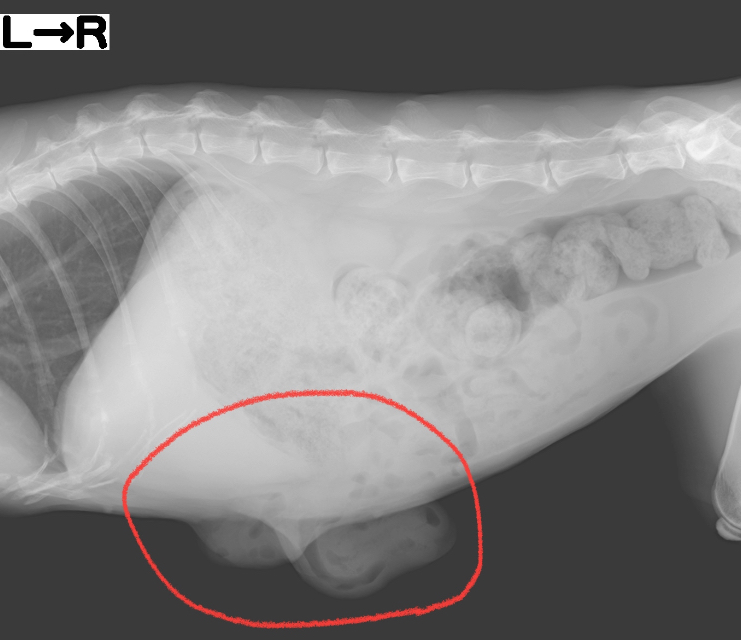

レントゲンを撮ってみると、、、

お臍の所と右側のお腹の所から脂肪組織や消化管の一部が飛び出てしまってます。

触診、レントゲンの結果から「腹壁ヘルニア」と診断しました。